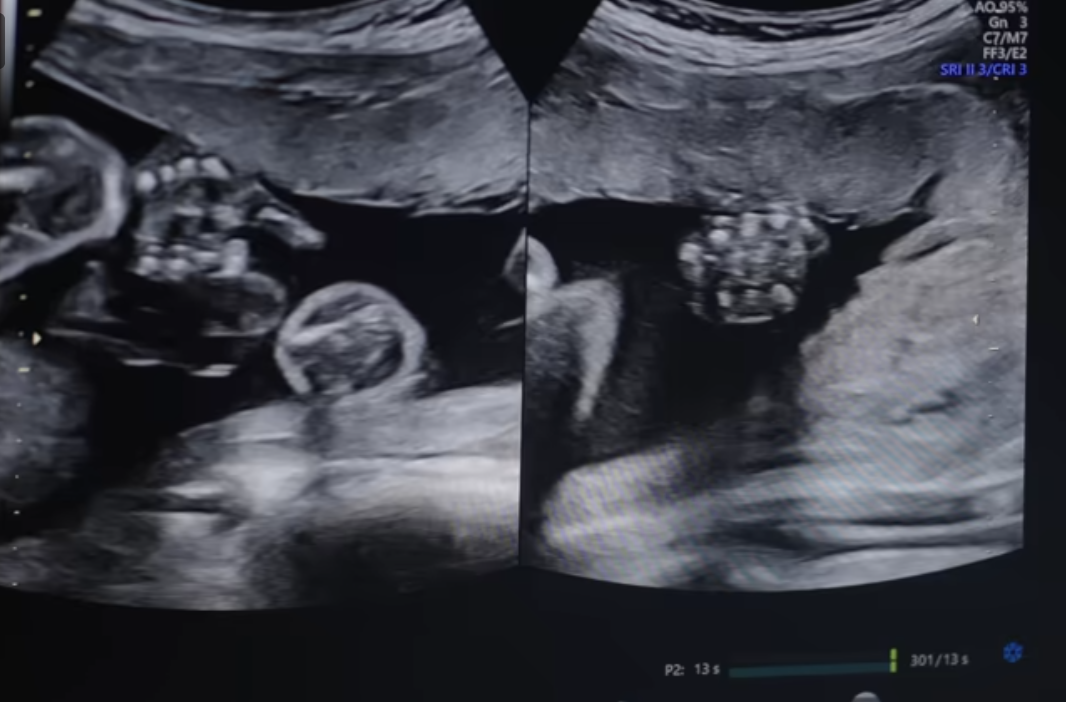

다태아 임신 관리의 핵심 요소

정기적인 산전 검진: 다태아 임신의 경우 일반 임신보다 더 자주 산전 검진을 받아야 합니다. 보통 2주마다 한 번 검진을 받는 것이 권장됩니다. 임신 16주부터 20주 사이에는 세부적인 초음파 검사를 통해 태반 위치, 태아 성장, 기형 여부 등을 확인합니다.

태아 성장을 모니터링하기 위해 2-4주마다 초음파 검사를 진행하며, 자궁경부 길이를 정기적으로 측정하여 조산 위험을 평가합니다.